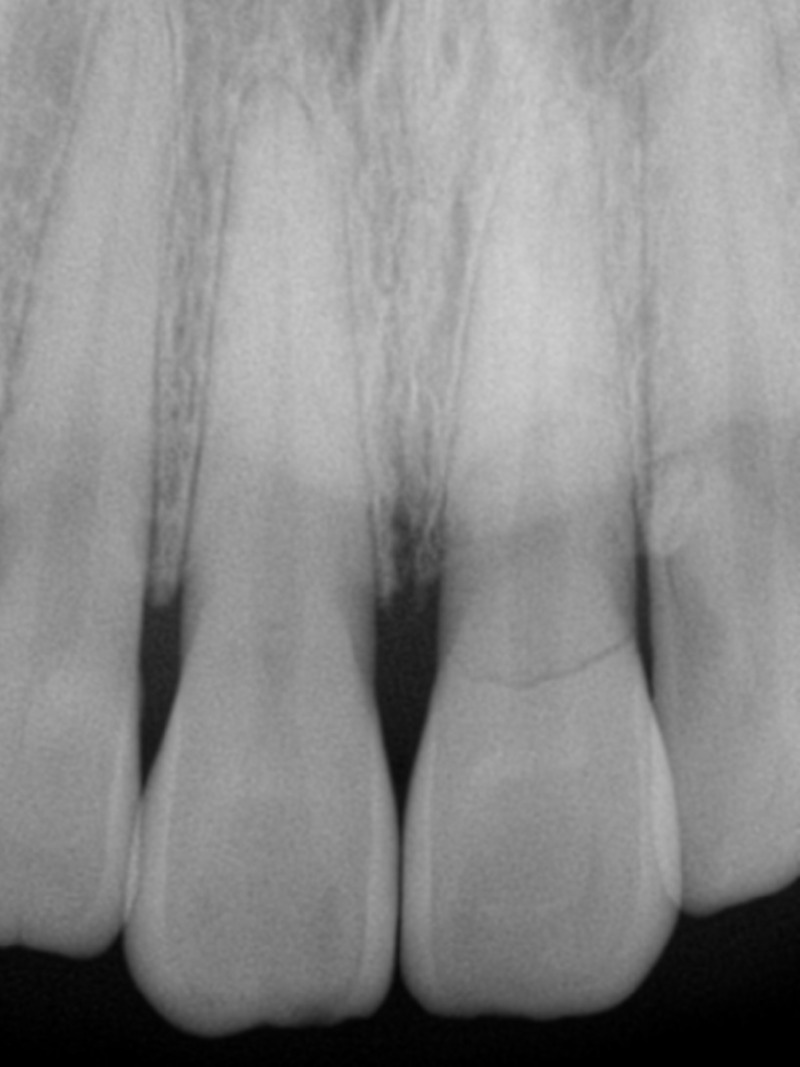

왼쪽 앞니는 뿌리 가까운 부분에서

완전히 부러졌습니다.

치아가 파절(부러짐)된 경우,

파절선(부러진 선)의 위치가 가장 중요합니다.

부러진 부분이 치아의 머리 끝 쪽에 가까울 수록

치아를 보존해서 쓸 수 있을 가능성이 높아지고

이 환자분의 경우처럼

잇몸보다 안 쪽의 뿌리에서 부러지는 경우는

치아를 보존하기가 어렵고,

어떻게든 시도해본다고 하더라도

치료의 예후가 좋지 않아

여러 번 고생하셔야 하는 경우가 많습니다.